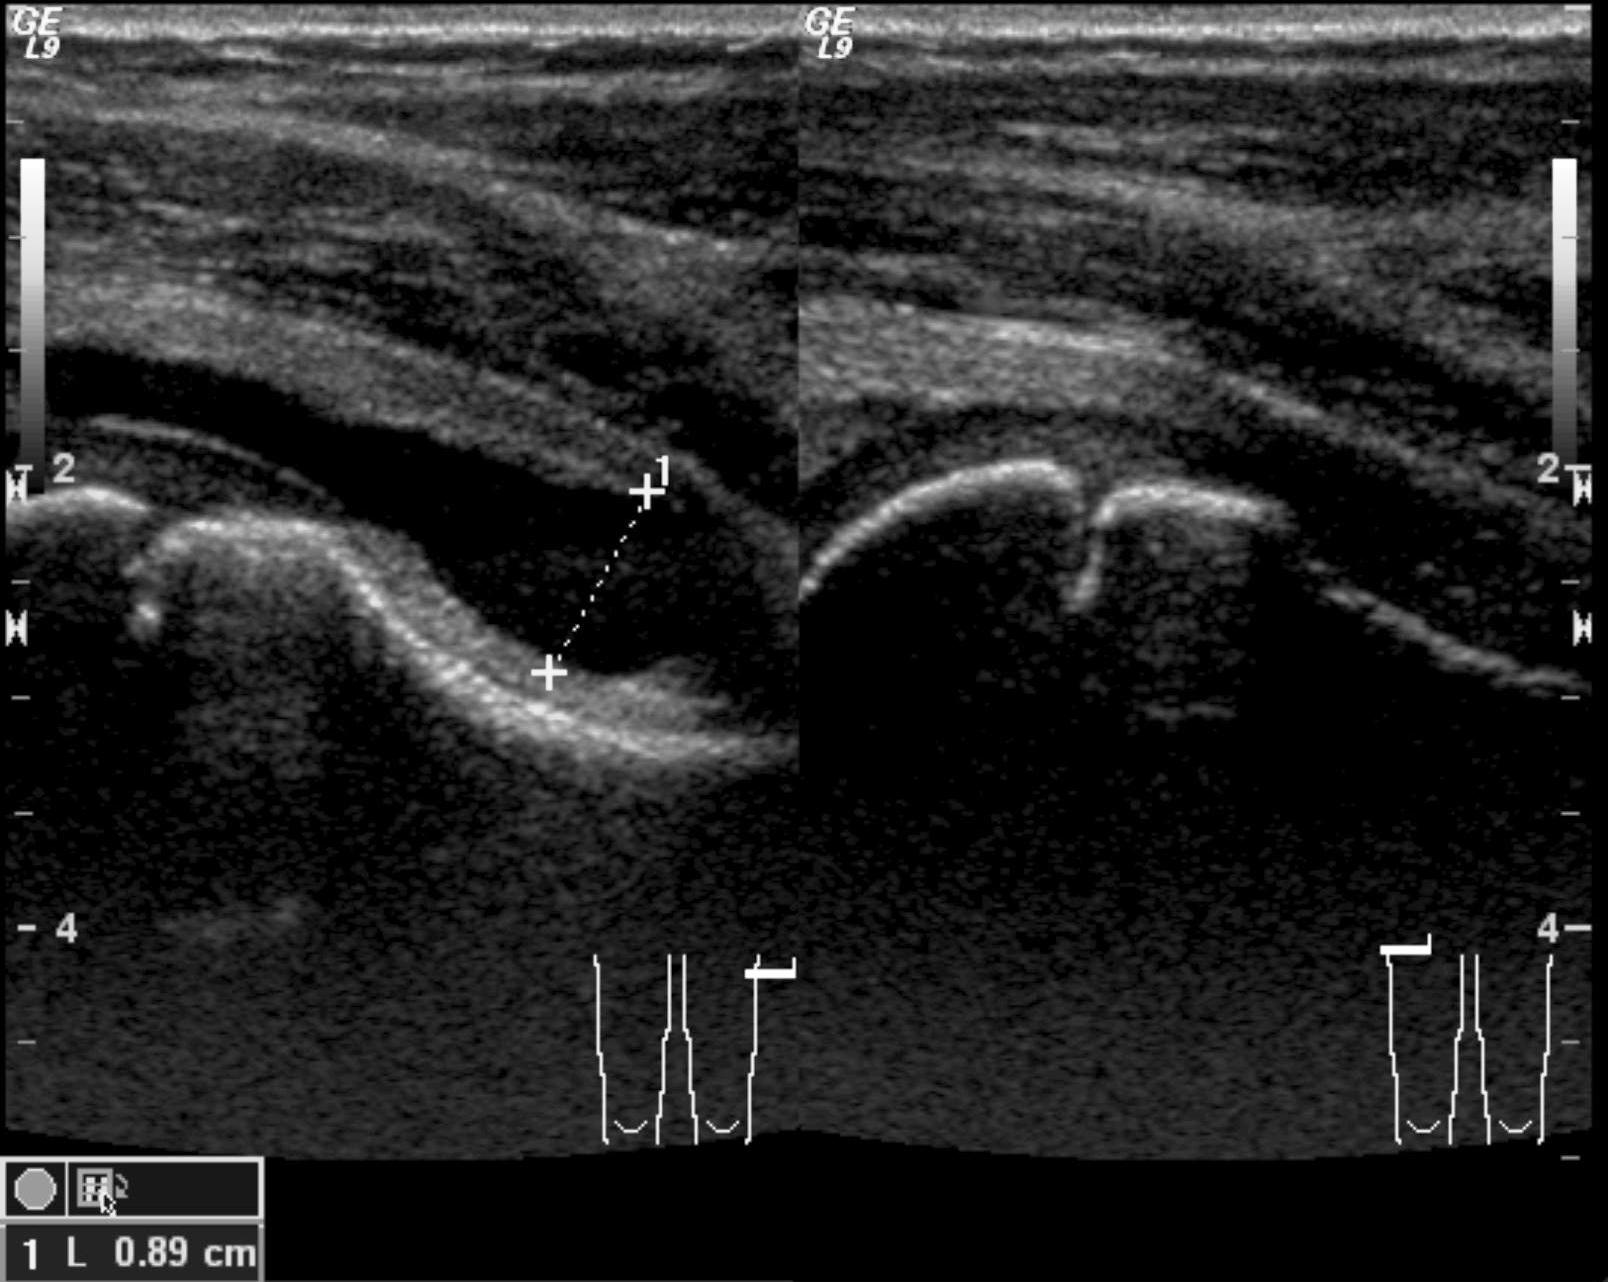

Image

38. US, longitudinal. On the proximal part of the right femur, the periosteal soft tissue is hypoechoic, the flow is increased. Osteomyelitis